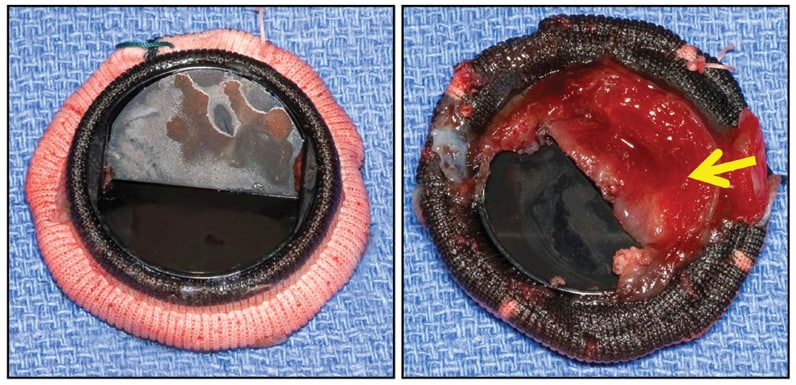

CarboMedics (29 mm) mitral valve prosthesis

CarboMedics (29 mm) mitral valve prosthesis

CarboMedics (29 mm) mitral valve prosthesis, with large shallow thrombus (arrow) entirely covering inflow aspect of one flap, completely immobilizing it, but without obstructive fibrous ingrowth (pannus).